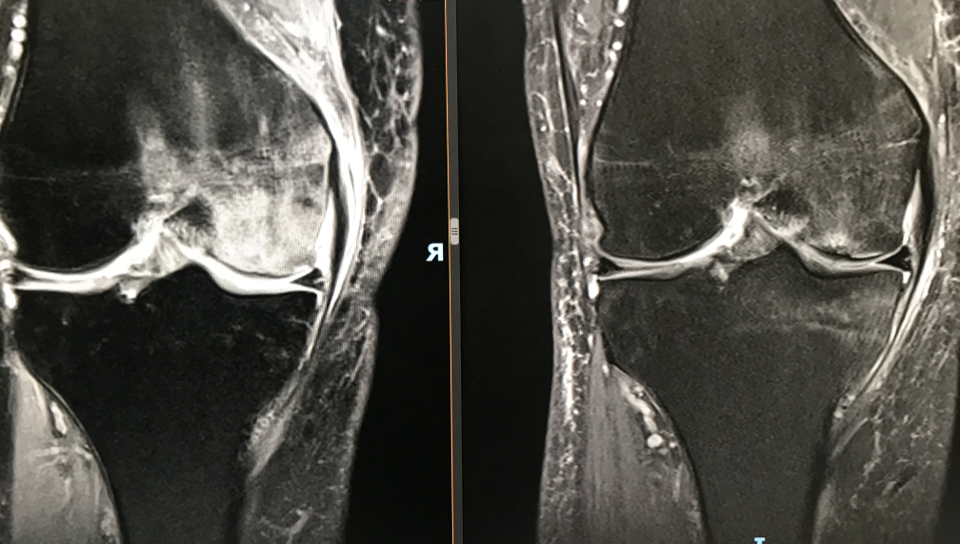

In this talk, James Youngman, Consultant Orthopaedic Surgeon at University College London Hospitals, explores orthopaedic pathology through the lens of engineering and physics, focusing on the behaviour of water in biological tissues. Drawing on clinical examples, imaging, and fundamental material properties, he explains how raised tissue pressure blocks blood flow, drives pain, and impairs healing—and why water, when trapped, can behave as a material far harder than bone.